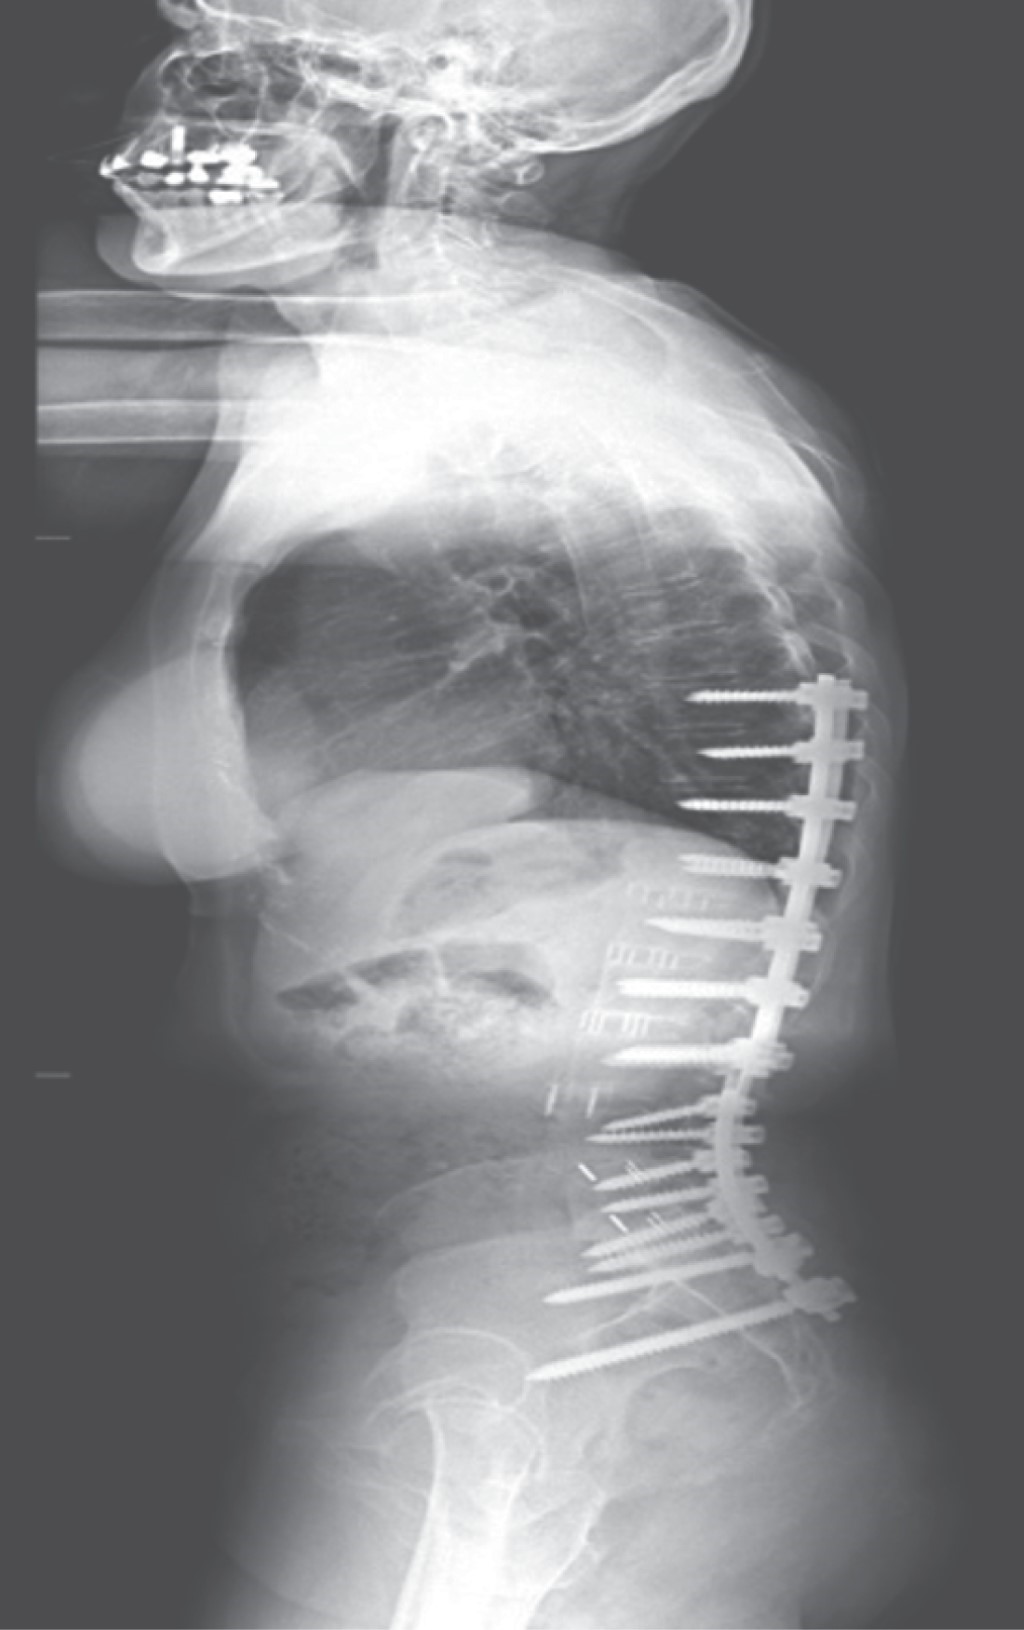

Mujer de 62 años acude a consulta con IMC de 24, sana, sin antecedentes patológicos por dolor axial lumbar y radicular izquierdo EVA 8/10, un Oswestry disability index (ODI) de 62% de seis meses de evolución, con intensificación en el último mes. Acude con imágenes panorámicas radiográficas de columna (Figuras 1 y 2), resonancia magnética (RMN) y tomografía computarizada (TAC) (Figuras 3 y 4).

Tratamiento: corrección de escoliosis, mixta XLIF T12 a L4, tornillos pediculares de T9-S1 con navegación O-ARM & StealthStation, (TLIF) de L5-S1 y fusión posterolateral (Figuras 5 y 6).

En el presente caso mediante la descompresión indirecta de XLIF y con TLIF apoyados en neuromonitoreo y navegación, se pudieron corregir curvas y compresión sin complicaciones ni falla en colocación de tornillos aun contando con anatomía distorsionada, recomendamos sustituir en la colocación de tornillos el uso de C-ARM por navegación con O-ARM. El riesgo de colocación fuera de pedículo de tornillos es < 1% con el uso de navegación, además disminuye la radiación al equipo médico y de sala de quirófano, siendo menor al uso de C-ARM en más de seis tornillos.